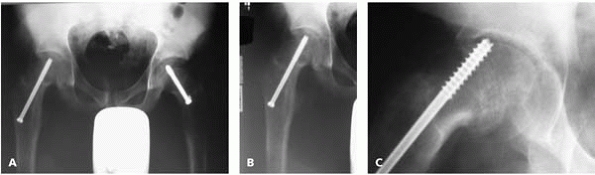

![]()  |

▪ FIGURE 22-14 Persistent hip pain after internal fixation of an SCFE requires careful evaluation. This AP pelvis image (A) and this AP of the right hip (B) do not show a clear source of the pain. This oblique image (C) shows the screw in the joint, with damage to the acetabulum. That certainly explains this patient’s persistent pain.

|